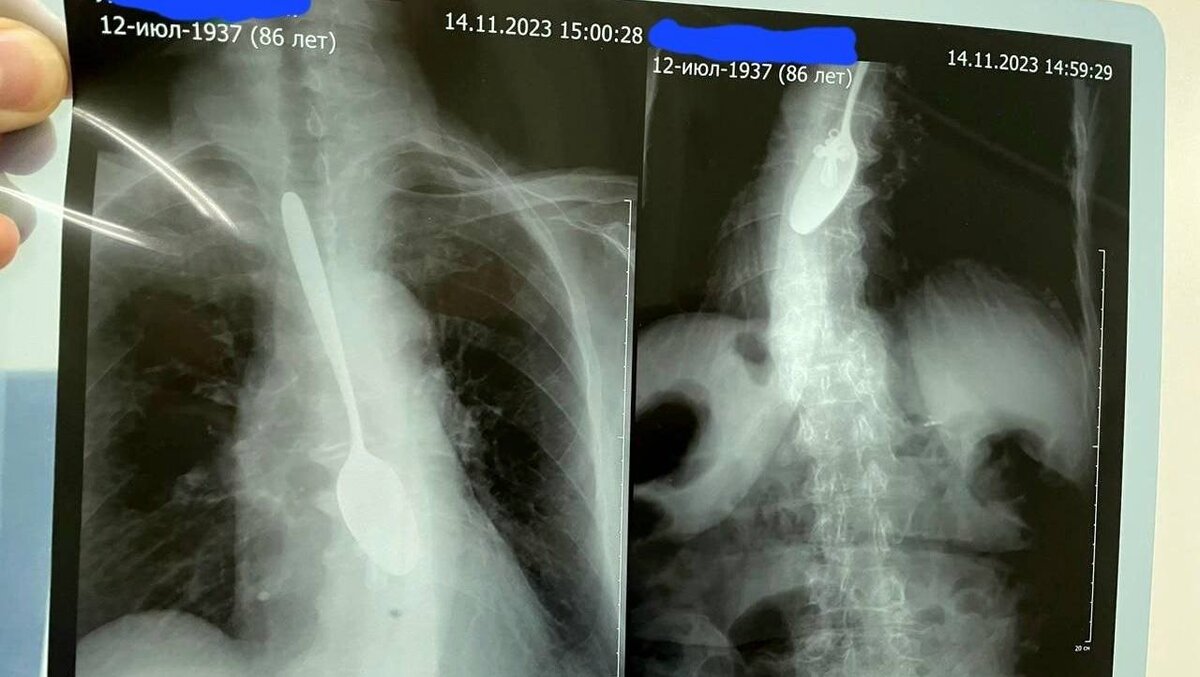

В Козьмодемьянской ЦРБ поступила 86-летняя бабушка, которая призналась врачам, что во время еды, случайно!, проглотила столовую ложку. Женщина во время обеда смотрела телевизор и настолько увлеклась происходящим на экране, что вместе с пищей съела и прибор. Команда докторов под руководством врача высшей категории Соколова Сергея Владимировича выполнила практически ювелирную работу по спасению пациента и изъятия инородного предмета. Ложку в итоге достали, при этом медикам удалось избежать возможной большей хирургической полостной операции. Бабушка жива и здорова. И очень довольна, ведь проглоченную ложку также вернули хозяйке.

В Козьмодемьянской ЦРБ поступила 86-летняя бабушка, которая призналась врачам, что во время еды, случайно!, проглотила столовую ложку. Женщина во время обеда смотрела телевизор и настолько увлеклась происходящим на экране, что вместе с пищей съела и прибор.

Команда докторов под руководством врача высшей категории Соколова Сергея Владимировича выполнила практически ювелирную работу по спасению пациента и изъятия инородного предмета.

Ложку в итоге достали, при этом медикам удалось избежать возможной большей хирургической полостной операции. Бабушка жива и здорова. И очень довольна, ведь проглоченную ложку также вернули хозяйке.